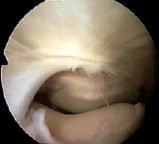

A plica may also be like a band of tissue. This image is of a suprapatellar plica viewed from the lateral suprapatellar portal, bowstringing and snapping across the supra patellar pouch over the medial femoral condyle. In this image, the red arrow is pointing to the plica. The little black arrows show the joint surface of the patella and femur.

The blue arrow shows the inflamed area of the femur where the plica has been snapping. This would be completely invisible from the lower portals.